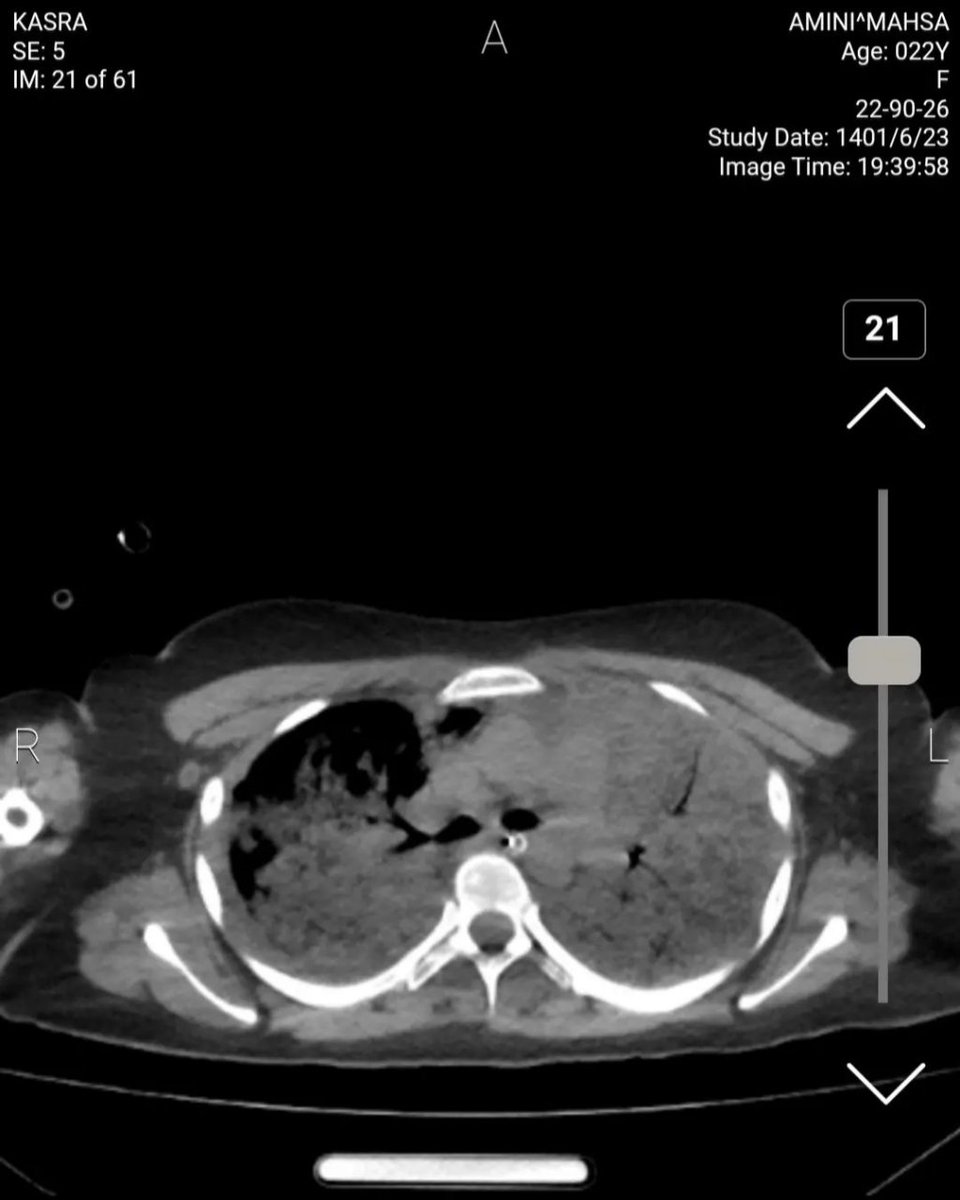

دکتر طاهریان، رزیدنت سال آخر رادیولوژی :

سلام. امروز موفق شدم به سی تی اسکن های مهسا امینی دسترسی پیدا کنم و به عنوان یک رزیدنت سال اخر رادیولوژی و پس از مشورت با یکی از اساتید و یکی از همکاران نوروسرجن ریپورت این سی تی اسکن رو خدمت شما میگم.

تصاویر بطورکامل درویندوهای مختلف ازطریق پکس بیمارستان کسری توسط بنده واستادوهمکار نوروسرجن بررسی شده.پیش ازهرچیزبگویم که پستم برای روشن شدن حقیقت درموردایشان هست وجنبه پزشکی ونه سیاسی دارد

پست من دردفاع ازشواهدیست که درسی تی اسکن ایشان دیده میشود نه دفاع یاحمله به کسی یاحکومتی Image